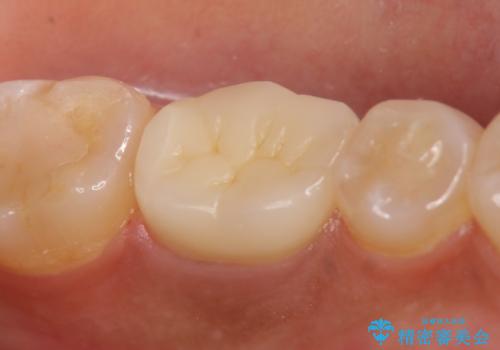

その後症状の緩解を確認後、オールセラミッククラウンによる補綴を行いました。

今回用いたオールセラミッククラウンはジルコニアフレームという白い素材の上にセラミックを盛っているため、審美性が非常に高いのが特徴です。

また、ジルコニアは人工ダイヤモンドの材料にも使われているほど高い強度を持っており、そのためオールセラミッククラウンは審美性だけでなく、奥歯やブリッジの補綴も可能とするクラウンです。